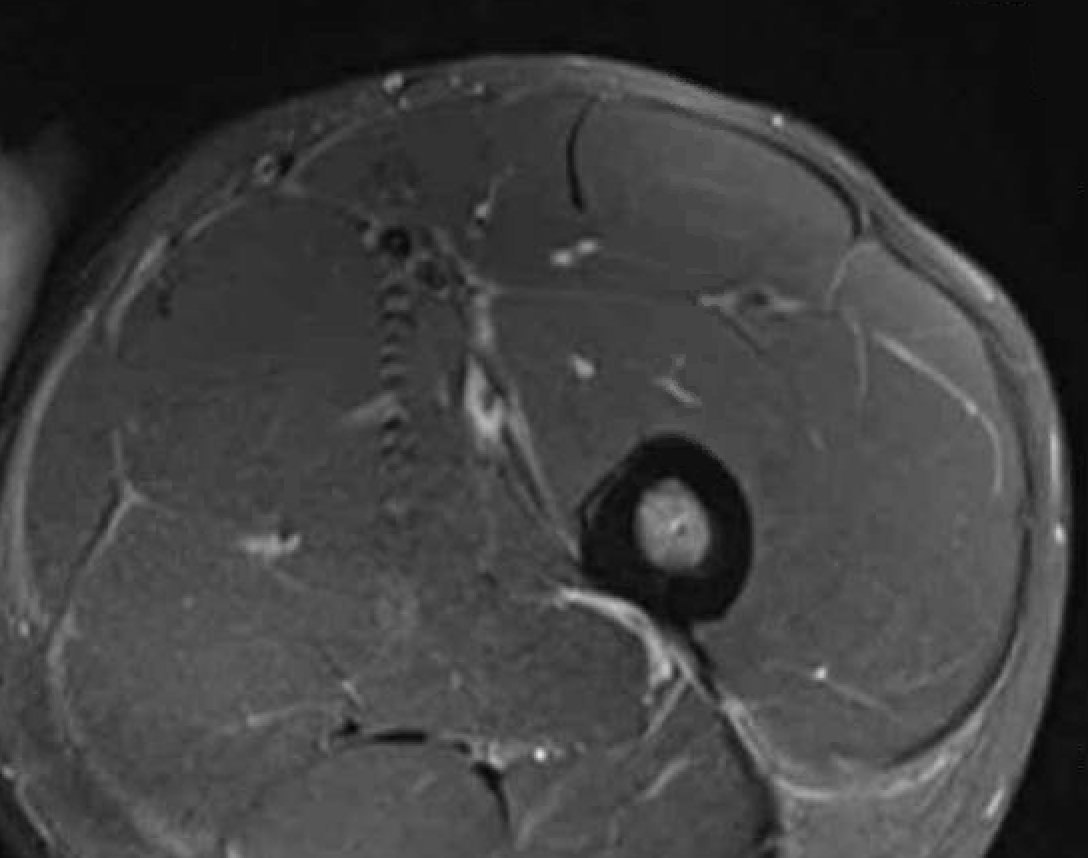

Chronic Grade 4 proximal rectus tear